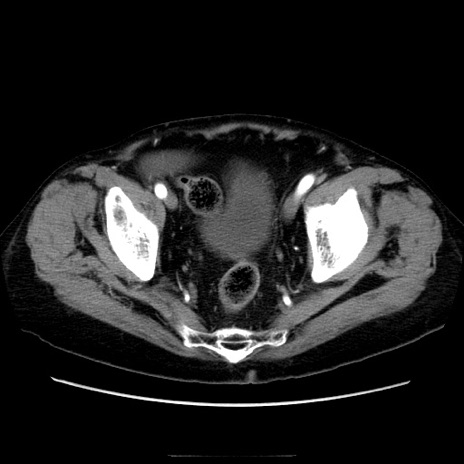

症例21(横断像)

【症例】70歳代男性

【主訴】腹痛

【現病歴】肝硬変・肝細胞癌にてかかりつけの方。約9時間前に食後より腹痛出現。症状が徐々に増悪し、嘔吐出現したため来院。

【既往歴】肝硬変、肝細胞癌(RFA、TACE後)

【身体所見】意識清明、表情苦悶様、BT 36℃、BP 129/78mmHg、P 88bpm、SpO2 97%(RA)、右上腹部から心窩部にかけて圧痛あり、反跳痛なし、筋性防御あり。

【データ】WBC 5800、CRP 0.16